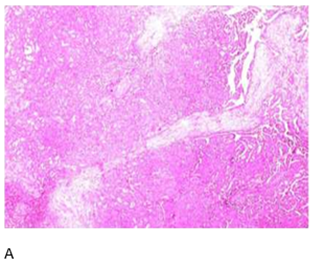

Histopathological

findings from a biopsy of the left retromolar trigone were consistent with CXPA

(Figure 2).

Figure 2. Hematoxylin

and Eosin:A: Low-power view

of salivary gland tissue infiltration by atypical ductal cells forming glands.

Cribriform pattern present; B: High-power view showing capsular invasion by

atypical ductal cells.